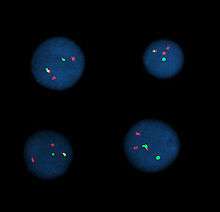

Fluorescent in situ hybridization

Fluorescent in situ hybridization (FISH) refers to using fluorescently labeled probe to hybridize to cytogenetic cell preparations.

This section refers to preparation of standard cytogenetic preparations

The slide is aged using a salt solution usually consisting of 2X SSC (salt, sodium citrate). The slides are then dehydrated in ethanol, and the probe mixture is added. The sample DNA and the probe DNA are then co-denatured using a heated plate and allowed to re-anneal for at least 4 hours. The slides are then washed to remove excess unbound probe, and counterstained with 4',6-Diamidino-2-phenylindole (DAPI) or propidium iodide.

Analysis

Analysis of FISH specimens is done by fluorescence microscopy by a clinical laboratory specialist in cytogenetics. For oncology generally a large number of interphase cells are scored in order to rule out low-level residual disease, generally between 200 and 1,000 cells are counted and scored. For congenital problems usually 20 metaphase cells are scored.